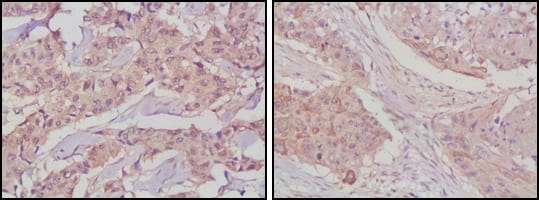

- Immunohistochemical analysis of paraffin-embedded human lung cancer (left) and breast cancer tissues (right) using GSK3B mouse mAb with DAB staining.